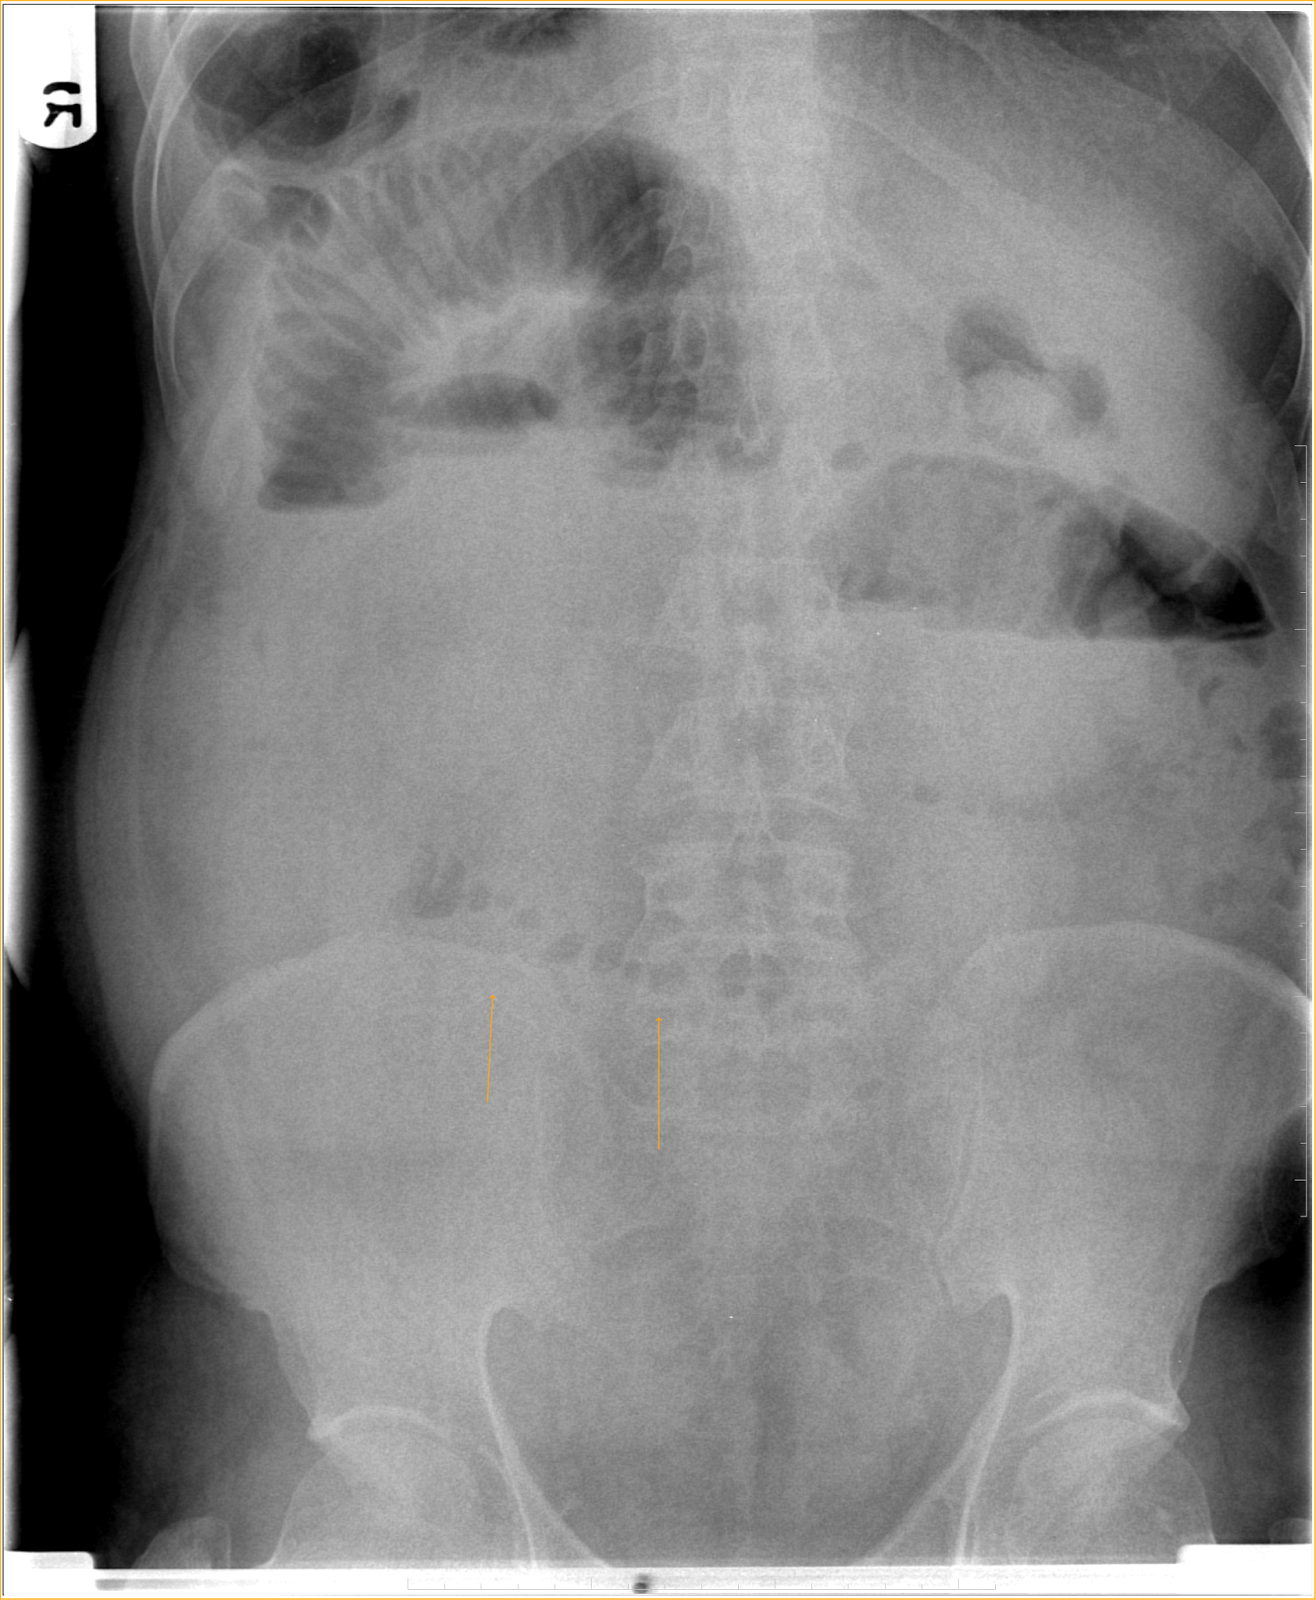

What Is A String-Of-Pearls Sign Mean . 1) has been associated with several conditions in the abdomen. The string of pearls sign metaphorically describes a radiographic finding highly suggestive of mechanical small bowel. When pcos is suspected and a. The term “string of pearls” or “crown of jewels” appearance denotes the presence of multiple tense vesicles and bullae. Ultrasound features for pcos diagnosis. This last symptom commonly presents as an ultrasound marker known as the string of pearls. This sign is also commonly referred to as the “string of beads” sign.

Small bowel obstruction string of pearls sign Image What Is A String-Of-Pearls Sign Mean 1) has been associated with several conditions in the abdomen. Ultrasound features for pcos diagnosis. This last symptom commonly presents as an ultrasound marker known as the string of pearls. When pcos is suspected and a. The term “string of pearls” or “crown of jewels” appearance denotes the presence of multiple tense vesicles and bullae. The string of pearls sign. What Is A String-Of-Pearls Sign Mean.

String of Pearls Sign (XRay) radRounds Radiology Network What Is A String-Of-Pearls Sign Mean 1) has been associated with several conditions in the abdomen. The term “string of pearls” or “crown of jewels” appearance denotes the presence of multiple tense vesicles and bullae. The string of pearls sign metaphorically describes a radiographic finding highly suggestive of mechanical small bowel. This last symptom commonly presents as an ultrasound marker known as the string of pearls.. What Is A String-Of-Pearls Sign Mean.